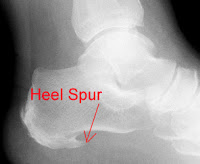

2. Heel SpurHeel spurs do not cause plantar fasciitis. It used to be thought that bony spurs found on the bone of the heel caused plantar fasciitis. However, there is no correlation between heel pain and the presence of a bony spur. Many people who never have had plantar fasciitis have heel spurs. The finding of a heel spur is an incidental finding but is often identified  (incorrectly) as the source of the pain. So if you have a spur, fear not, with proper treatment you should be able to recover form plantar fasciitis and return to activity.